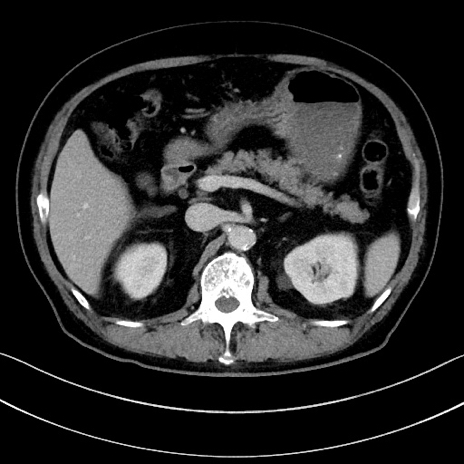

症例15(横断像)

【症例】70歳代男性

【主訴】腹痛

【現病歴】今朝から腹痛あり。全体的に痛い。特に左上の方。排ガスが今日はない。冷や汗が出る。

【既往歴】直腸癌術後

【身体所見】左側腹部〜上腹部に圧痛あり。腹膜刺激症状明らかなではない。軽度反跳痛。左下腹部に術後瘢痕あり。

【データ】WBC 7700、CRP 0.02